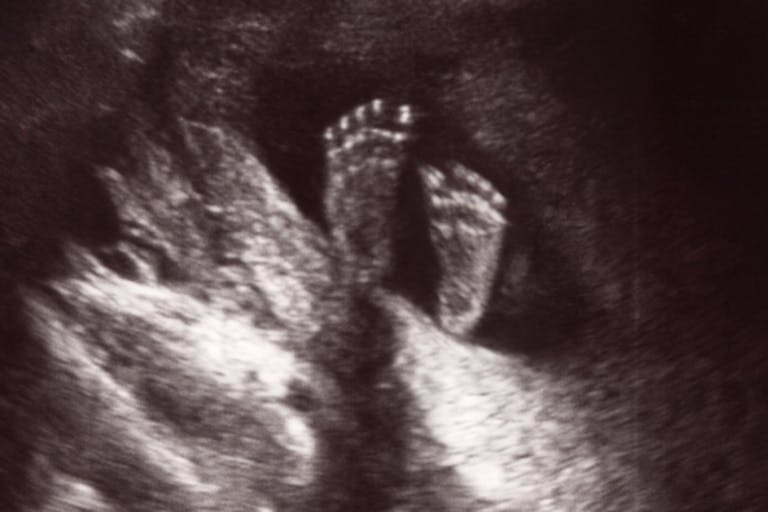

A “fetus” is a mammal in the fetal stage of development, which in humans starts at the beginning of the 11th week of gestation (9 weeks after fertilization). Prior to that, the human child is in the embryonic stage (“embryo”). After the embryonic stage, the child remains in the fetal stage of development. Here is an embryo at 8 weeks post-fertilization, or 10 weeks gestation — immediately prior to the fetal stage: